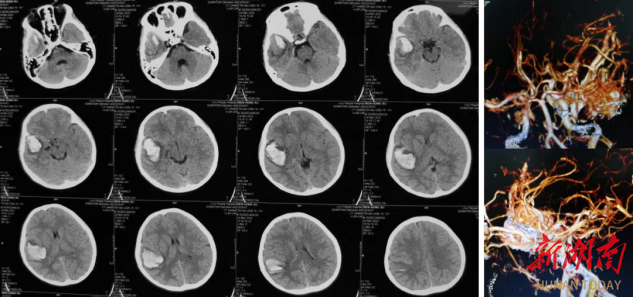

事发当天,张先生正朝着每日100个俯卧撑的目标努力,做到第89个时突然重重砸在瑜伽垫上。他挣扎起身时,突然感到钢针刺进太阳穴般的剧烈头痛,还伴随天旋地转的眩晕感,根本无法站立。家人见状立即拨打120急救电话,将其紧急送医。经头颅CT检查,张先生被确诊为运动相关性脑出血,出血量达15毫升。神经外科・NICU主任钟治军带领团队迅速开展紧急救治,最终助其脱离生命危险。